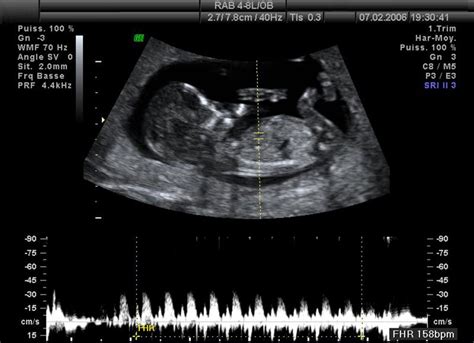

Klasický 2D ultrazvuk: Základná diagnostika

Napriek pokročilým technológiám zostáva klasický 2D ultrazvuk základným diagnostickým nástrojom v tehotenstve. Väčšina gynekológov má tento prístroj vo svojich ambulanciách a práve na ňom mnoho budúcich mamičiek vidí svoje dieťa prvýkrát. 2D ultrazvuk poskytuje dvojrozmerný obraz, ktorý lekárom umožňuje zhodnotiť základné parametre tehotenstva, ako je umiestnenie embrya v maternici, počet plodov, vitalitu, presnú dĺžku tehotenstva a odhaliť prípadné anomálie maternice či vajíčkovodov.